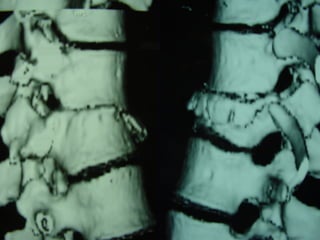

3D CT -SCAN

 AANN.. PPEERR..

 FF –– 2222 yyrrss

 FFaallll

 LLeevveell :: TT1122

 TTyyppee :: AA33..33

 AA..SS..II..AA.. :: EE